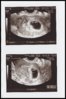

Viikkoja olikin vasta 5+6 (6+6 oli neuvolassa laskettu), mutta kaikki oli hyvin. Ehkä oon vaan tulossa hulluksi ja kuvittelen itelleni kaikki oireet